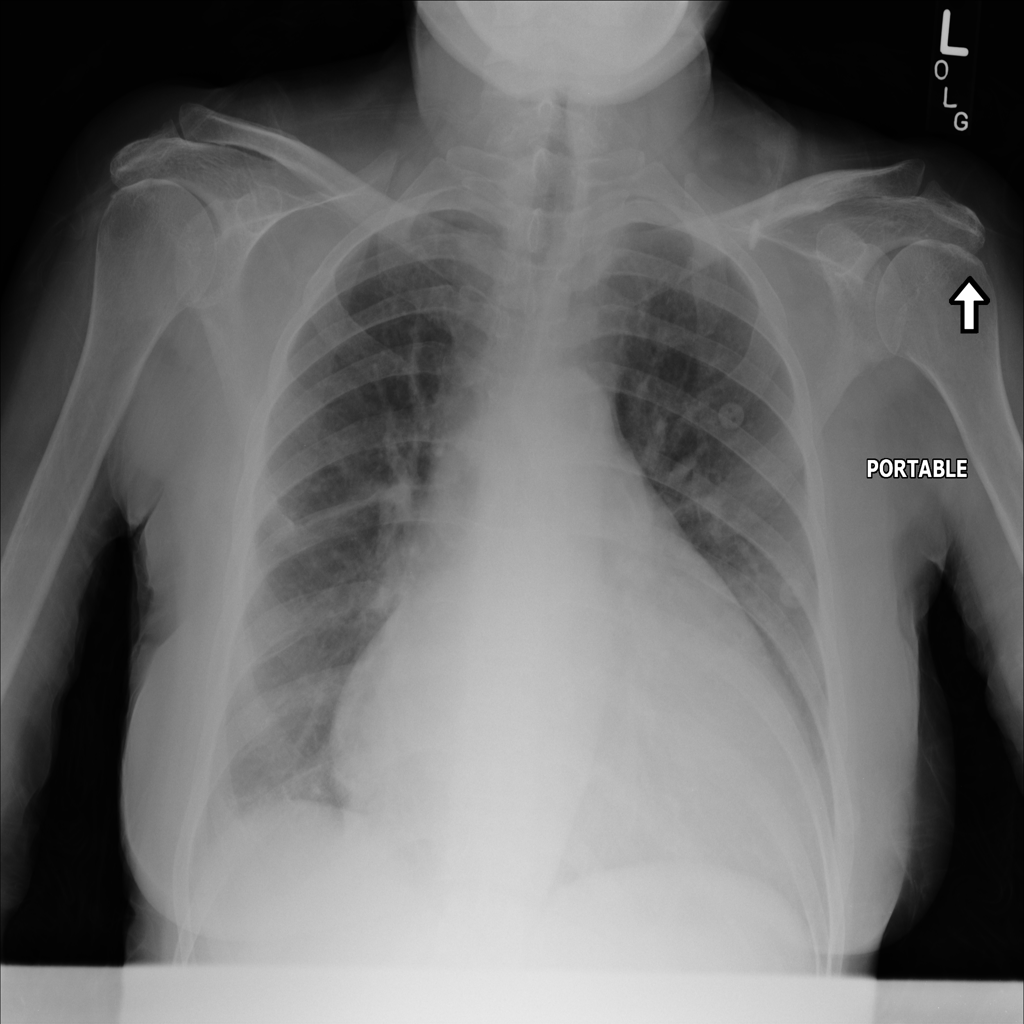

PAT-3384 · IMG-000Cardiomegaly

PAT-3384 · IMG-000

AP